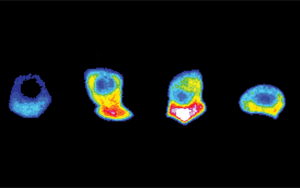

近日,來自牛津大學(xué)等研究機(jī)構(gòu)在Nature上發(fā)表了題為“SARS-CoV-2 is associated with changes in brain structure in UK Biobank”的研究成果(圖1),研究表明COVID-19會(huì)導(dǎo)致患者大腦的整體體積有所萎縮,萎縮的腦組織損傷與認(rèn)知功能缺陷相關(guān),也影響嗅覺等功能。即使是輕癥患者也不例外。